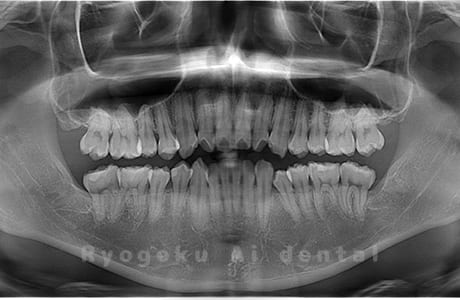

水平埋伏の親知らず

歯茎の中で完全に横に生えてしまうタイプです。

この親知らずを水平埋伏智歯と言います。このタイプはほとんどが下顎のケースです。真横に生えているので抜歯の際は難易度が高く2~3つに砕いて分けて抜歯をします。